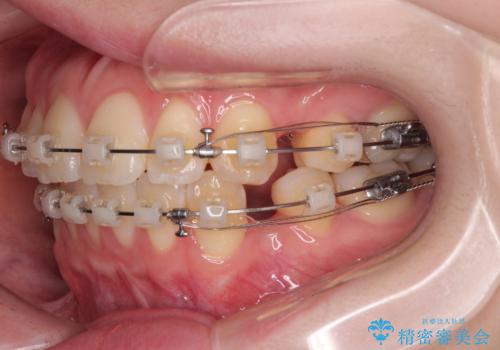

- 矯正装置

- クリアブラケット

- くちばしのように飛び出した前歯を気にして来院された患者様です。

上下左右の第一小臼歯4本を抜歯して、ワイヤー装置にて矯正治療を行うこととしました。

舌の突出癖により、口元が突出しているだけでなく、上下前歯が非接触となっておりました。

舌のトレーニングをしっかりと行っていただくことで、2年を切って治療を終えるとともに

、上下前歯を接触させることができました。